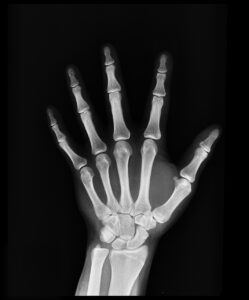

ACL断裂は、前十字靭帯が完全に切れてしまう状態を指します。この靭帯は、膝関節の安定性を保つ重要な役割を果たしており、特にサッカーなどのスポーツでは、その機能が非常に重要です。